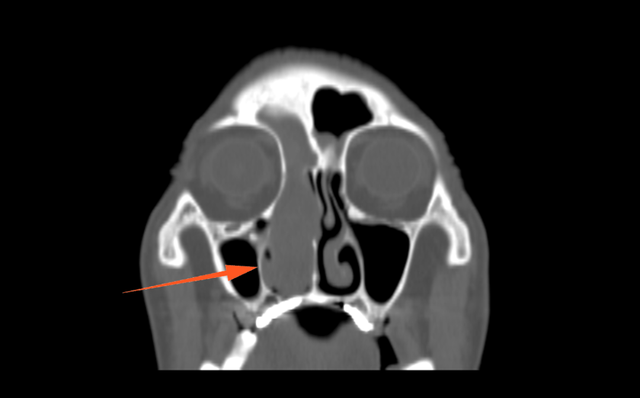

CT显示:右侧鼻腔及额窦、筛窦

又充满了软组织影

进一步增强MR显示:鼻腔右侧异常信号影,T1等信号,T2等高信号,DWI高信号,增强后周边强化为主。

蒋主任仔细阅读影像学图像,该患者的肿物在T2相有 “脑回征”,但又不典型,鼻窦骨质也没有明显的增生,肿物已经占满整个右侧额窦窦腔,好在患者额窦气化尚可,肿物未越过瞳孔中线,要彻底清除肿物,需要打开额窦,将窦内软组织完全清理干净并磨除基底部部分骨质再烧灼。